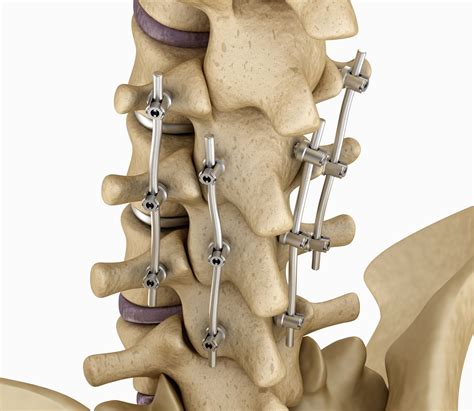

• Posterior Cervical Fusion: This approach involves accessing the spine from the back of the neck. It is often used for conditions that affect the posterior elements of the spine, such as spinal instability or fractures.

• Fixation: Plates, screws, or other fixation devices may be used to stabilize the vertebrae and promote fusion.